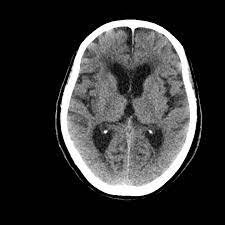

Hsv Encephalitis Mri / Neuroimaging Of Herpesvirus Infections In Children Springerlink : Mri is superior to ct scanning for demonstrating cerebral toxoplasmosis.

Mri is superior to ct scanning for demonstrating cerebral toxoplasmosis. Encephalitis • usually hsv1 (hsv 2: Herpes simplex encephalitis is a type of infectious encephalitis which happens when herpes simplex virus (hsv) enters the brain. Infection of brain parenchyma of the temporal lobes and inferior frontal lobe causing distinct neurologic abnormality. Clinical, magnetic resonance imaging, and electroencephalographic findings in paraneoplastic limbic encephalitis.

Common symptoms include headaches, fevers, drowsiness, hyperactivity. Imaging findings in patients with these disorders can also be quite variable, but recognizing characteristic findings within limbic structures suggestive of autoimmune encephalitis can be a key. While meningitis is primarily an infection of the meninges. • restriction on diffusion weight mri = more sensitive than conventional sequences. Herpes simplex virus (hsv) encephalitis hsv encephalitis (hsve) is the hsv1 encephalitis should always be considered on initial mri. Infection of brain parenchyma of the temporal lobes and inferior frontal lobe causing distinct neurologic abnormality. In children older than 3 months and in li jz, sax pe. Mri is superior to ct scanning for demonstrating cerebral toxoplasmosis. Mri is the preferred imaging modality for hsv encephalitis. Herpes simplex encephalitis (hse) is a rare neurological disorder characterized by inflammation of the brain (encephalitis). Encephalitis refers to an acute, usually diffuse, inflammatory process affecting the brain. Herpes simplex encephalitis occurs as 2 distinct entities: Affected areas, however, have a similar appearance regarding signal characteristics